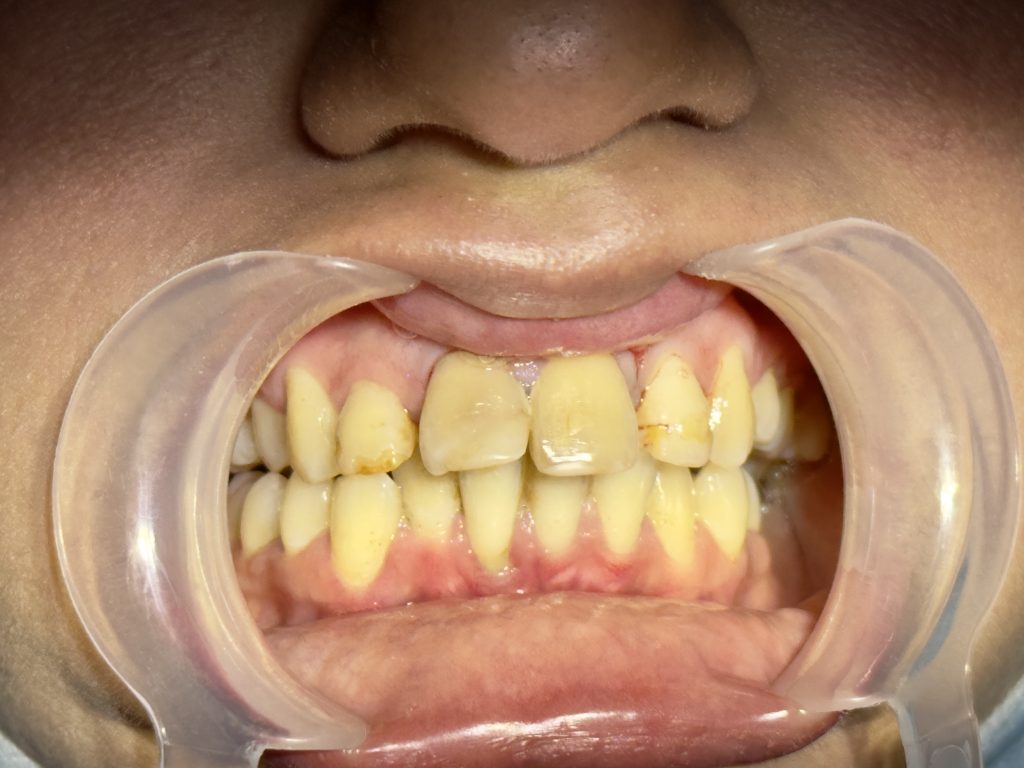

Chief Complaint

“I don’t like my smile. My front teeth are discolored and uneven. I want a natural and beautiful smile, but I cannot go for braces.”

- Moderate discoloration of tooth #11 and #21.

- Slight midline discrepancy; patient declined orthodontic correction.

- Post-traumatic discoloration due to pulpal necrosis.

- Residual esthetic defect after apexification.

- Asymmetrical incisal edges, smile cant, and uneven gingival margins.

- Reduced incisal guidance.